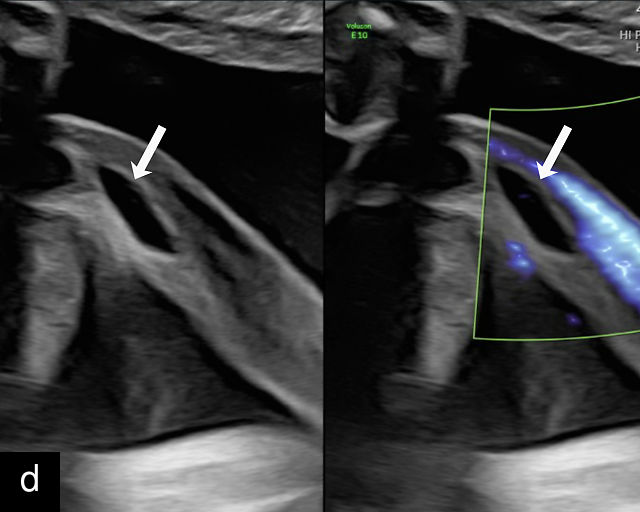

21

(a) Type-1 vasa previa. Photograph after delivery showing the umbilical cord inserting into the membranes through which unprotected fetal vessels run to insert into the placental edge. (b) Type-2 vasa previa. Photograph after delivery showing bilobed placenta with unprotected fetal vessels running though the membranes between the lobes. (c) Type-3 vasa previa in a twin pregnancy. Photograph after delivery showing unprotected vessels running through the membranes from one edge of the placenta to another (arrow). (d) Transabdominal grayscale ultrasound of the lower uterine segment showing a linear hypoechoic structure (fetal vessel) running over the cervix (c) indicating vasa previa (Type 2). b, bladder; h, fetal head. (e) Transabdominal color Doppler ultrasound of the lower uterine segment showing fetal vessels (arrow) running over the cervix (c) indicating vasa previa (Type 2). (f) Transabdominal ultrasound with color flow and pulsed-wave Doppler of the lower uterine segment showing a fetal vessel running over the cervix (c) indicating vasa previa (Type 2). Pulsed-wave Doppler demonstrates an umbilical arterial waveform. (g) Transvaginal grayscale ultrasound with showing a Type-2 vasa previa. There are two placental lobes, an anterior (a) and a posterior (p) lobe. There is a linear and circular hypoechoic structure (arrow) running over the cervix (c) between the lobes. (h) Transvaginal grayscale ultrasound image of vasa previa. A hypoechoic linear structure (arrow) is seen running through the membranes over the cervix (c). h, fetal head. (i) Transvaginal grayscale ultrasound of vasa previa. Hypoechoic circular and linear structures are seen close to the internal os. (j) Transvaginal color Doppler ultrasound image of vasa previa. A fetal vessel is seen running through the membranes over the internal os (arrow) of the cervix (c). h, fetal head. (k) Transvaginal ultrasound with color Doppler showing a Type-2 vasa previa. There are two placental lobes, an anterior and posterior lobe (pl). Fetal vessels run over the cervix between the lobes. (l) Transvaginal color flow ultrasound with pulsed-wave Doppler image of vasa previa. Color Doppler shows flow through the vessel and pulsed-wave Doppler shows a fetal umbilical venous waveform. (m) Transvaginal color ultrasound with pulsed-wave Doppler image of vasa previa. Color flow Doppler shows flow through the vessel and pulsed-wave Doppler shows a fetal umbilical arterial waveform. (n) Transvaginal three-dimensional ultrasound with color Doppler image of vasa previa. h, fetal head; c, cervix.

12